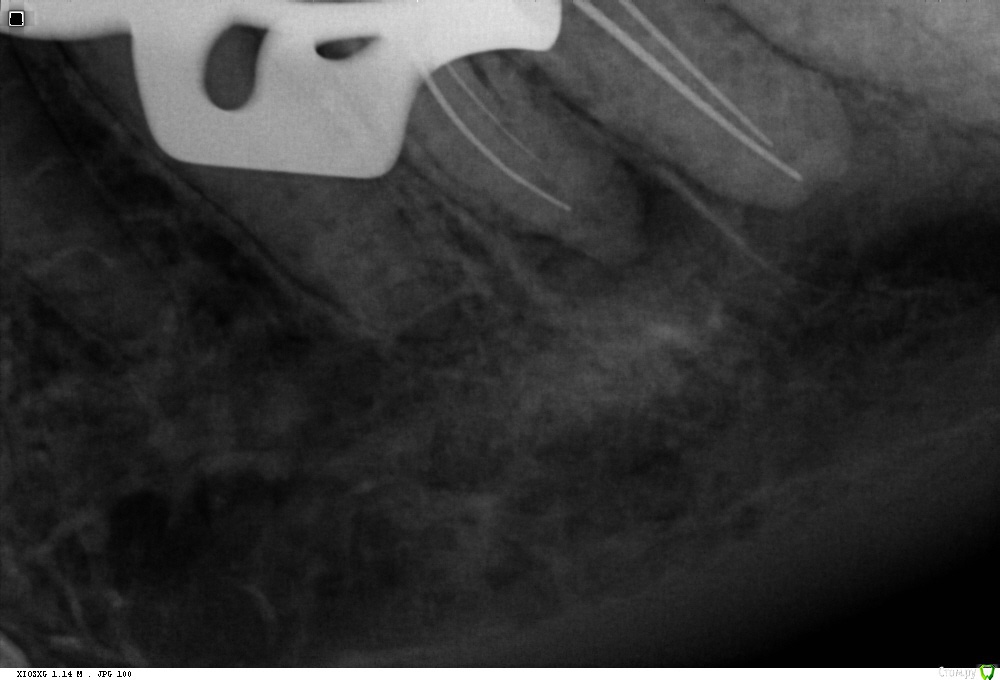

St. Опубликовано 30 января, 2018 Поделиться Опубликовано 30 января, 2018 До, с инструментом и после. Испортила немного картинку после выведенным силлером Ссылка на комментарий